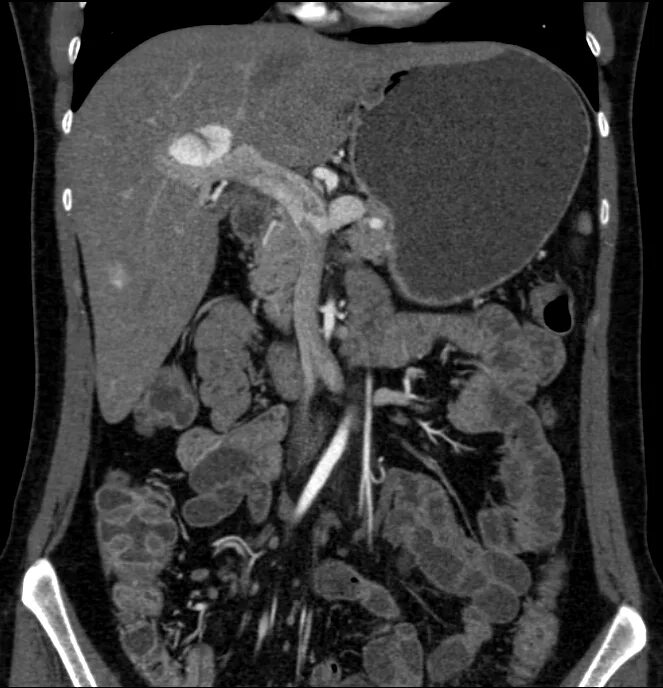

Метастазы в желчном